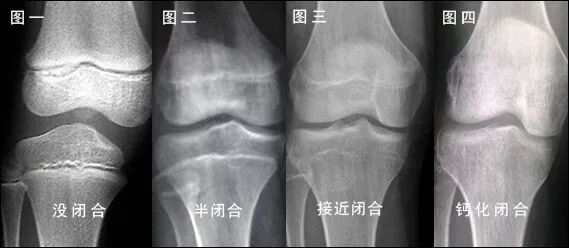

有呀。一般小朋友要長高,骨骼生長功不可沒,長骨的兩端存在著非常特殊的區域——骨骺和生長板,骨骼變長就是通過這一區域的生長來實現的。同時,隨著年齡的增長,骨骺的生長逐漸緩慢,生長板逐漸變薄,最終完全與骨骺融合后便不會生長,人也就不能繼續長高。因此,我可以用來判斷骨的發育程度,預測兒童的成年后身高,此外還能為某些內分泌疾病、營養障礙的診斷提供參考。